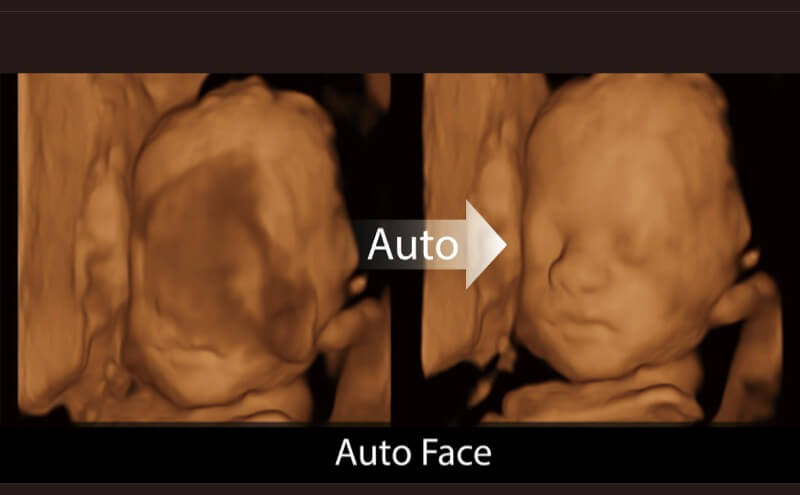

Die Visualisierung des 3D-Gesichts des Fetus ist wichtig für die Diagnose von Gesichtsanomalien. Durch Auto Face können Hindernisse und Artefakte wie Nabelschnur, Plazenta, Gebärmutter und Extremitäten einfach entfernt werden, um eine optimale Ansicht des fetalen Gesichts zu erhalten.